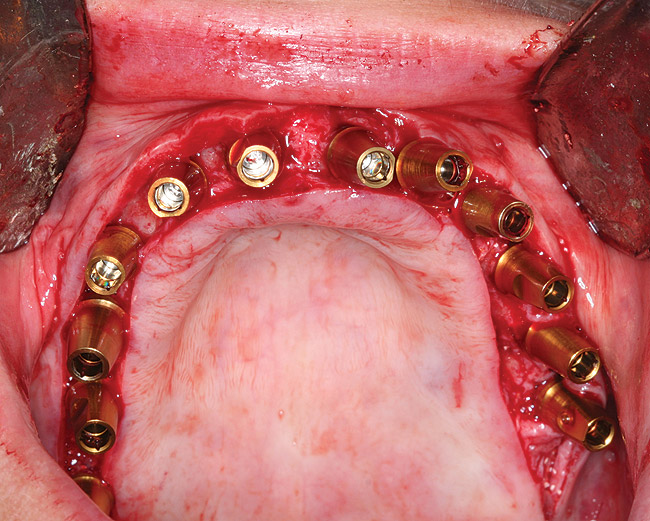

After 6 months of healing, a CBCT scan was taken and good bone formation was seen on the axial (Figure 18) and panograph (Figure 19) views. The CBCT was then used to plan for placement of dental implants (Figure 20). Upon full-thickness reflection of the ridge, abundant bone contour was observed. Internal hex dental implants (BioHorizons) were placed according to the locations planned on the CBCT (Figure 21). After a healing period of 4 months, the implants were uncovered (Figure 22) and abutments were placed (Figure 23). A panograph taken 1 year after this stage revealed the final restorations on well-integrated implants (Figure 24). The patient’s smile reveals a fixed prosthesis that simulates her natural teeth (Figure 25).

Figure 23  Clinical view of abutment placement.

Figure 23